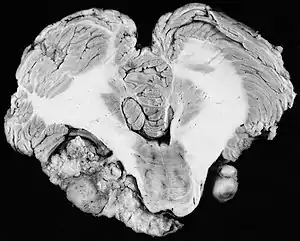

![]() | |

| Bilateral schwannomas in a patient with neurofibromatosis 2 | |

In the early 1900s the mortality rate for VS surgery was in the range of 75 to 85%. Surgeons typically delayed invasive intervention as long as possible as a last resort. Harvey Cushing (1869–1939) is known as 'the father of neurosurgery for VS.' His basic study published in 1917 was entitled Tumors of the Nervus Acusticus and the Syndrome of the Cerebellopontine Angle. Cushing perfected the retrosigmoid surgical approach, and by doing suboccipital craniotomy and subtotal removals he was able to reduce mortality to 4% by 1931. Cushing worked at Brigham Hospital in Boston. An equally famous specialist for VS at Johns Hopkins in Baltimore was Walter E. Dandy (1886–1946), a former pupil of Cushing who advocated total tumor removals. In 1931, he reported a complete removal with preservation of the facial nerve.